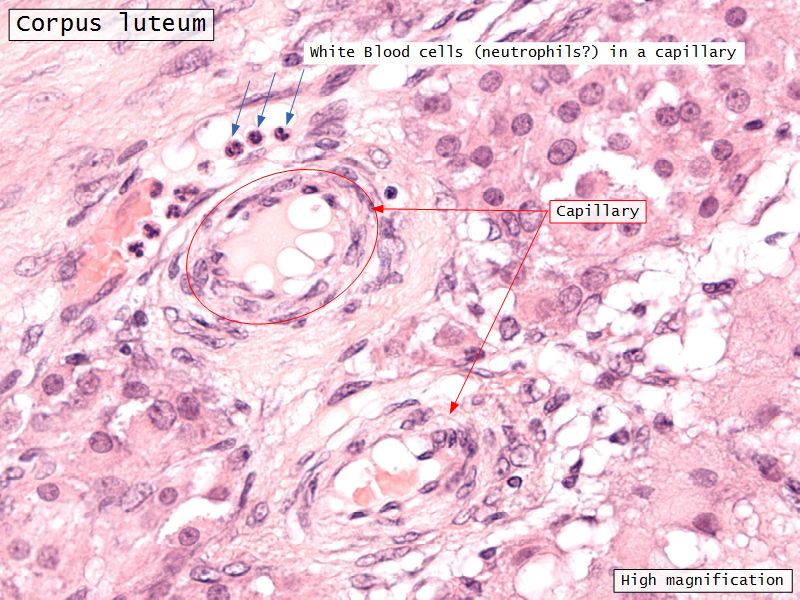

Corpus luteum

Slide 91

Corpus luteum

- Two major cell types

- Many capillaries